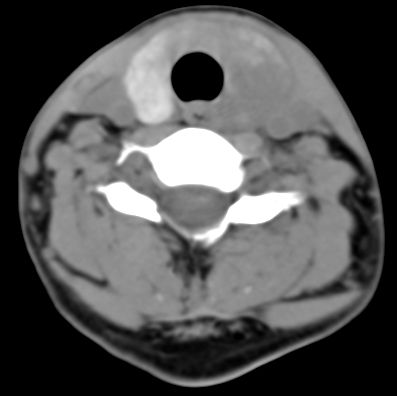

标题: CT9717:F、30Y、颈部左侧包块半年,压痛.患者拒绝作增强。 [打印本页]

标题: CT9717:F、30Y、颈部左侧包块半年,压痛.患者拒绝作增强。

左侧甲状腺增大,密度降低,性质不好定,还是作个增强,或作核素扫描.

甲状腺弥漫增大,以左叶明显,内见不均匀低密度影,边缘模糊欠清,周围脂肪间隙模糊。

左侧甲状腺及甲状腺狭部弥漫性增大,边缘模糊,未见明确界线.考虑甲状腺炎可能性大.

左侧甲状腺弥满性增大,其内密度均匀减低,气管无受压。周围结构清晰。考虑甲状腺炎可能性大。

甲状腺弥漫增大,以左叶明显,左侧内见不均匀低密度影,边缘模糊欠清,周围脂肪间隙模糊。

甲状腺弥漫性增大病变有以下几种.

1,结节性甲肿;起病慢,无压痛.t3\\t4升高或正常,一般双侧肿大,密度较高.部分可囊变钙化,增强后结节状轮廓显示清楚.轻度强化.

2,亚急性甲状腺炎.临床多见,发病年龄较轻,由上呼吸道感染或病毒性腮腺炎后发病.临床触痛明显.然局部皮肤无红热.t3t4早期升高,后期降低.病灶可单侧或双侧.易炎性渗出,使脂肪密度增高.

3,桥本甲炎(慢性淋巴细胞性甲炎);自身免疫有关.t3t4降低.中老年女性多见.甲状腺弥漫增大,基本对称.,峡部最明显.边界较清.